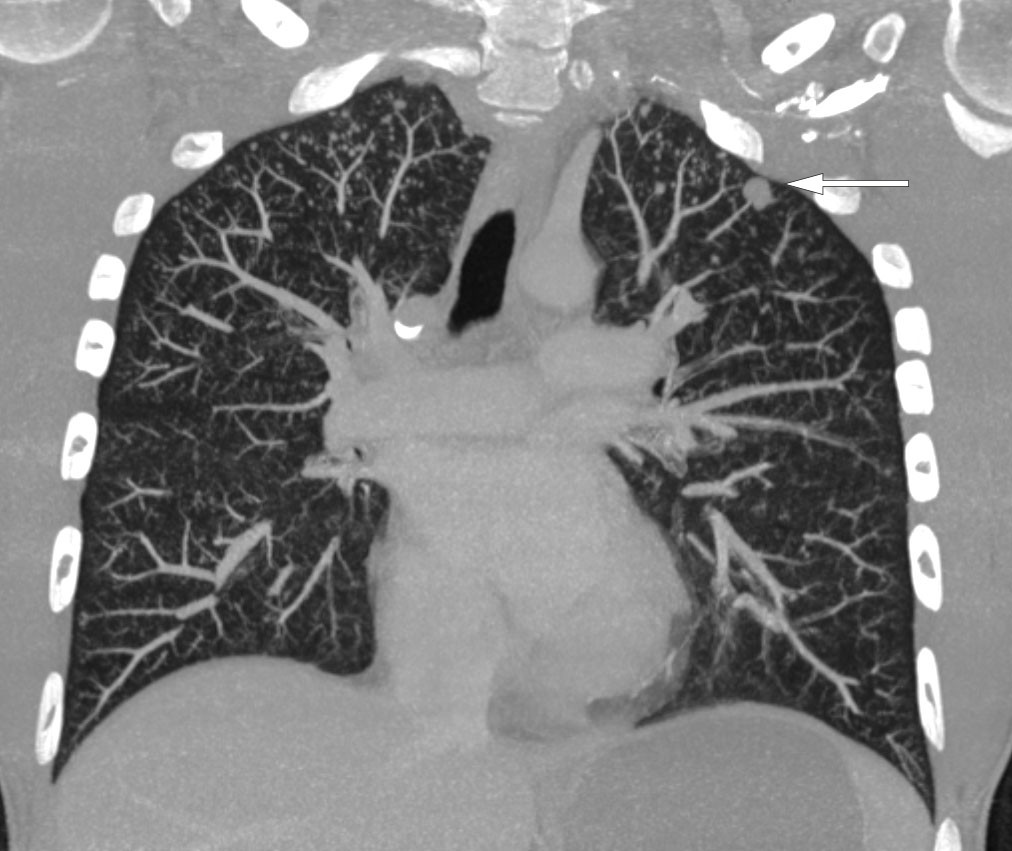

CT-undersøkelse uten kontrast av hodet ble tatt umiddelbart etter innleggelse og viste lavattenuerende forandringer i hvit substans frontalt i høyre storhjernehemisfære (fig 1) og i høyre lillehjernehemisfære. Supplerende magnetisk resonanstomografi av hjerne og medulla påfølgende dag avdekket multiple lesjoner i hjernestamme, lillehjerne og begge storhjernehemisfærer (fig 2). Nevroradiolog vurderte funn som forenlig med multiple metastaser, hjernetuberkulose, parasittsykdom eller septiske embolier med sekundær abscessdanninger. Spinalvæskeundersøkelse viste leukocyttnivå på 9 · 109/l, men ellers normale verdier for erytrocytter, glukose og protein. Det ble samme kveld utført CT av thorax, abdomen og bekken for å se etter tegn til ekstracerebral sykdom, inkludert kreft, bakterielt infeksjonsfokus, tuberkulose i eller utenfor lunger, eventuelt tegn til parasittsykdom. Denne avdekket multiple mikronoduli i lungene, mest i apikale deler av begge overlappene, én litt større nodulus apikalt og lateralt i venstre overlapp samt en liten høyattenuerende lesjon til høyre for avgangen av høyre hovedbronkus som var forenlig med en forkalket lymfeknute (fig 3). Det var multiple lavattenuerende lesjoner i abdomen og bekken, mest i øvre del av lever, og i tillegg lesjoner i nyre og prostata. Radiologen beskrev funnene som mest forenlig med miliær tuberkulose.